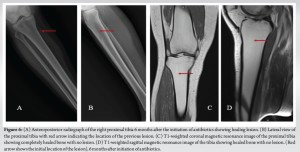

The tissue samples were sent for histopathological examination, culture and sensitivity, and X-PERT analysis for tuberculosis. The culture grew Salmonella spp. Sensitivity pattern showed the organism to be resistant to amikacin, ciprofloxacin, gentamycin, levofloxacin, and cefaperazone-sulbactam. It was sensitive to ofloxacin, ceftriaxone, amoxicillin- clavulanic acid, and ertapenem. The X-PERT analysis was negative for tuberculous bacilli. Species identification of the bacillus could not be done. The histopathological examination showed acute inflammatory exudate with necrotic tissue, consistent with features of osteomyelitis of femur. Postoperatively, we ruled out sickle cell disease by a peripheral smear. She was started on intravenous ertapenem based on the MIC level and continued for 6 weeks, followed by 2 weeks of oral cotrimoxazole. Only partial weight-bearing with support was allowed till 6 weeks postoperatively, full-weight-bearing thereafter. She presented for follow-up on day 7, 14, 6 weeks, 3 months, 6 months, and 1 year postoperatively. Serial CRP level monitoring was done. Follow-up radiograph showed healing of the cortex and integration of the antibiotic beads (Fig. 4 and 5). Repeat MRI was done at 6-month mark postoperatively which showed healed lesions at both mid shaft of femur and proximal tibia (Fig. 6). The patient is currently asymptomatic and doing all activities of daily living.